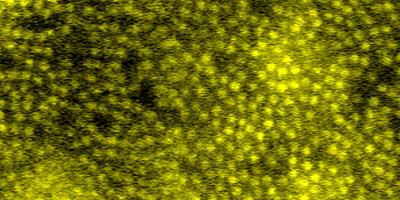

neuron vessels

Inner retinal capillaries (top) and choriocapillaris (bottom) imaged in a living human eye using multimodal adaptive optics enhanced indocyanine green angiography.